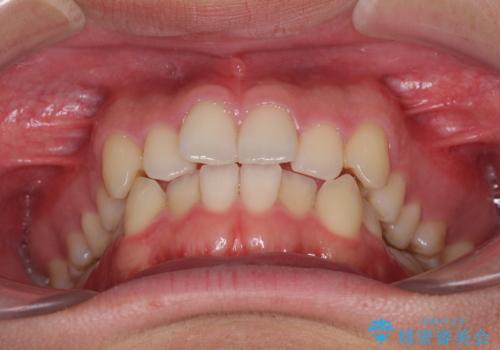

狭い歯列と前歯のデコボコ インビザラインによる矯正治療

- 上下前歯のデコボコを気にして来院された患者様です。

インビザラインによる上下歯列の拡大と、IPR(歯と歯の間を削る)にるスペースの獲得により、前歯のデコボコと狭い歯列を改善することとしました。

比較的軽度な歯列不正であったため、治療期間はそれほど長くはならないと予想されました。

しかしながら、あまりしっかりとマウスピースを装着していなかったため、思いの外期間が長引いてしまいました。

また、仕上がりの歯列にも若干の叢生が残ってしまいました。